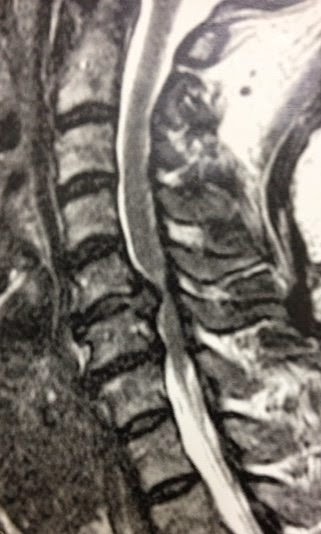

A foto mostra um aneurisma da artéria cerebral media após dissecção do vale Sylviano e preparo do seu colo para a clipagem. A foto foi tirada de um smartphone através da lente do microscópio, um antigo DF Vasconsellos, que ainda é muito utilizado para este tipo de neurocirurgia.

| Aneurisma da artéria cerebral média. |